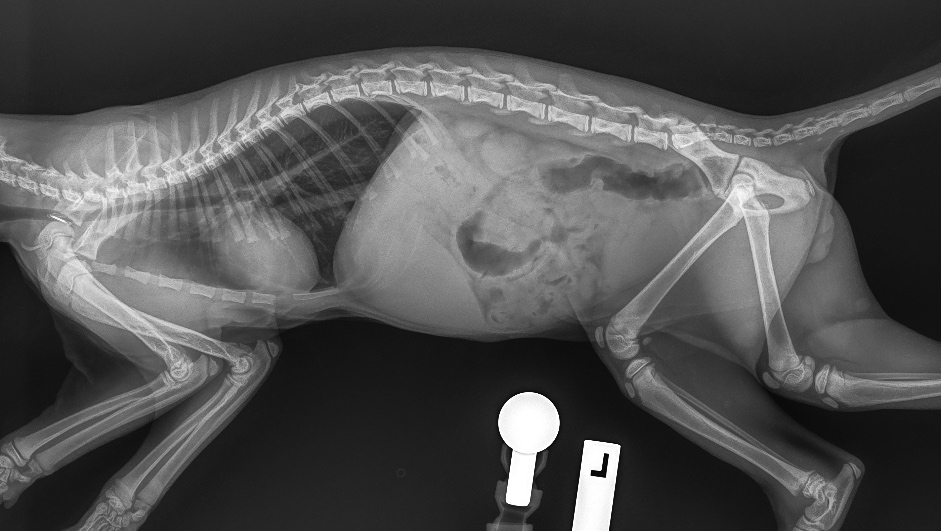

The Whyalla Veterinary Clinic has a new Shimadzu MUX10 Xray machine for high quality radiographs and a new Agfa XD14 Csi Tethered panel to produce outstanding direct digital Xrays from the images from the Shimadzu MUX10 Xray machine.

The XD14 CsI Tethered Panel is an integral part of an Agfa HealthCare’s Instant DR solution, which includes the NX image acquisition software with MUSICA3 processing and detector. These cassette-less and filmless solutions provide a range of workflow benefits that improve quality, productivity and speed up exam time.